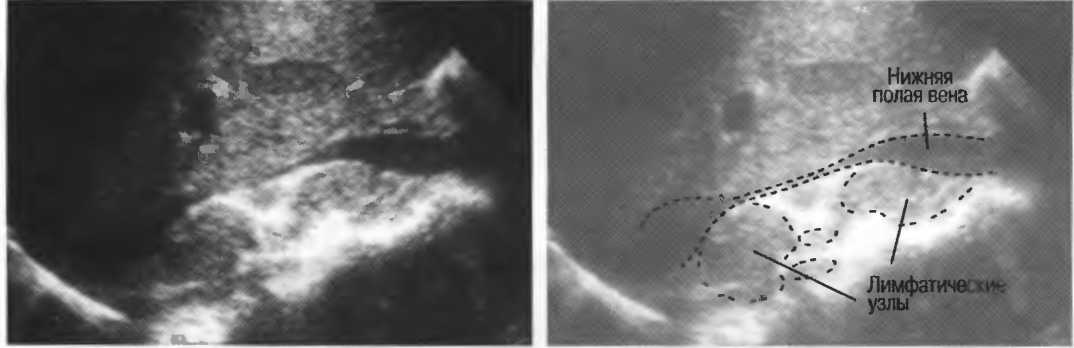

Газ отражает ультразвук и экранирует ткани, расположенные сзади, в результате преломления и акустической тени от газа. Газ в кишечнике может экранировать печень, поджелудочную железу, парааортальные лимфоузлы, матку, яичники. Иногда удается сместить газ в кишечнике, например при наличии наполнения мочевого пузыря матка и яичники почти всегда легко визуализируются, так как кишечные петли «убраны» из поля зрения. В других случаях бывает необходимо делать косые, латеральные или дорсальные сканы в положении пациента стоя или сидя (рис. 19).